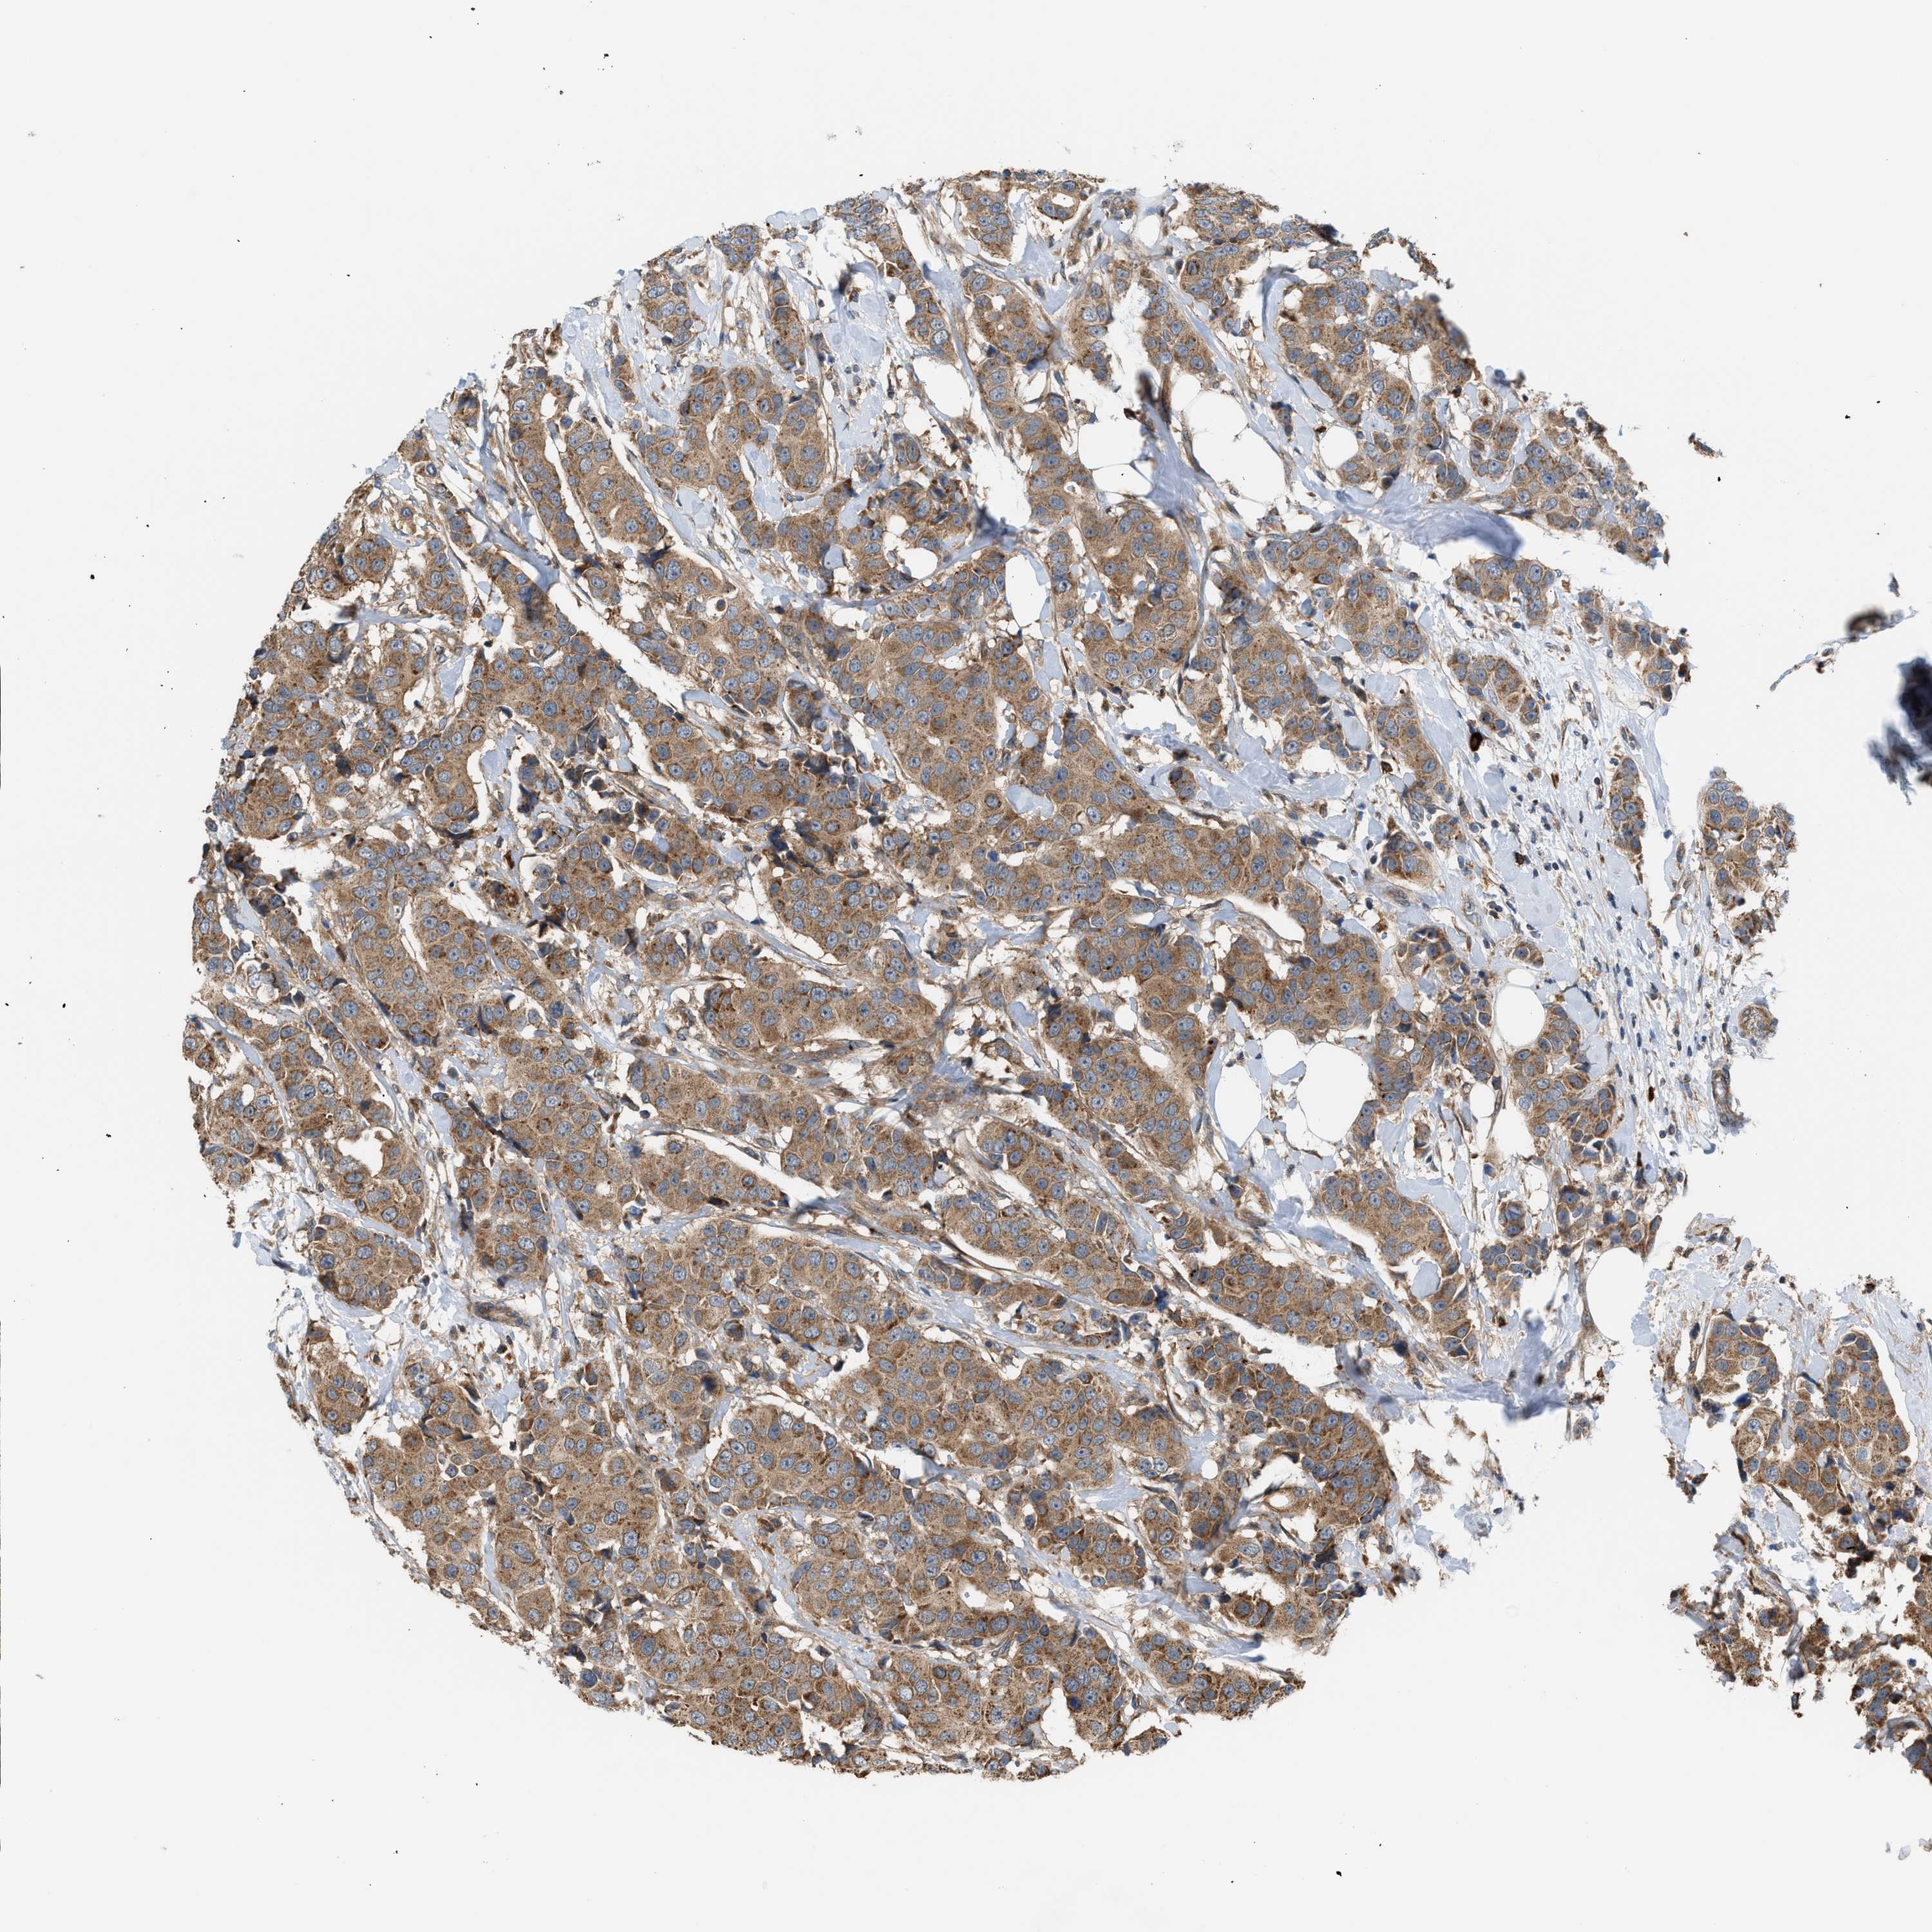

CANCER BREAST CANCER Show tissue menu

BRCA TCGA BRCA VALIDATION PROTEIN EXPRESSION